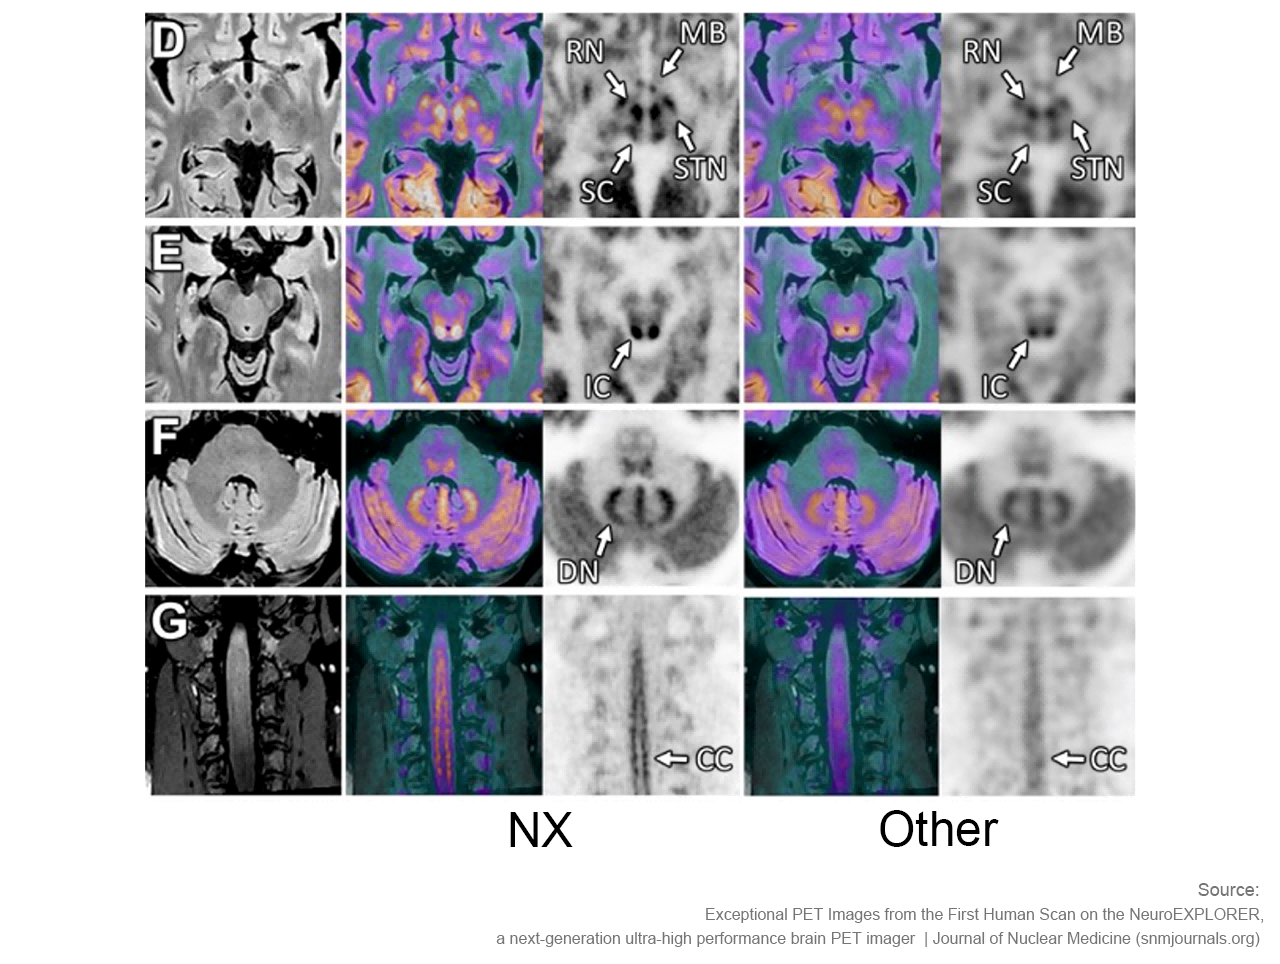

NeuroExplorer (NX)产出的脑部影像图

NeuroExplorer拥有基于NEMA NU 2-2018标准的超高灵敏度:46cps/kBq,同时配备着先进的时间飞行技术,进一步增强了NX的综合性能。

卓越空间分辨率 洞察大脑微观

小型探测器元件确保最精微的结构能被检测,甚至探查特定脑核中的神经递质运动。搭载1.5mm的有效空间分辨率,带来前所未见的解剖细节。

NeuroExplorer (NX)产出的脑部影像图与其他设备产出的脑部影像图对比